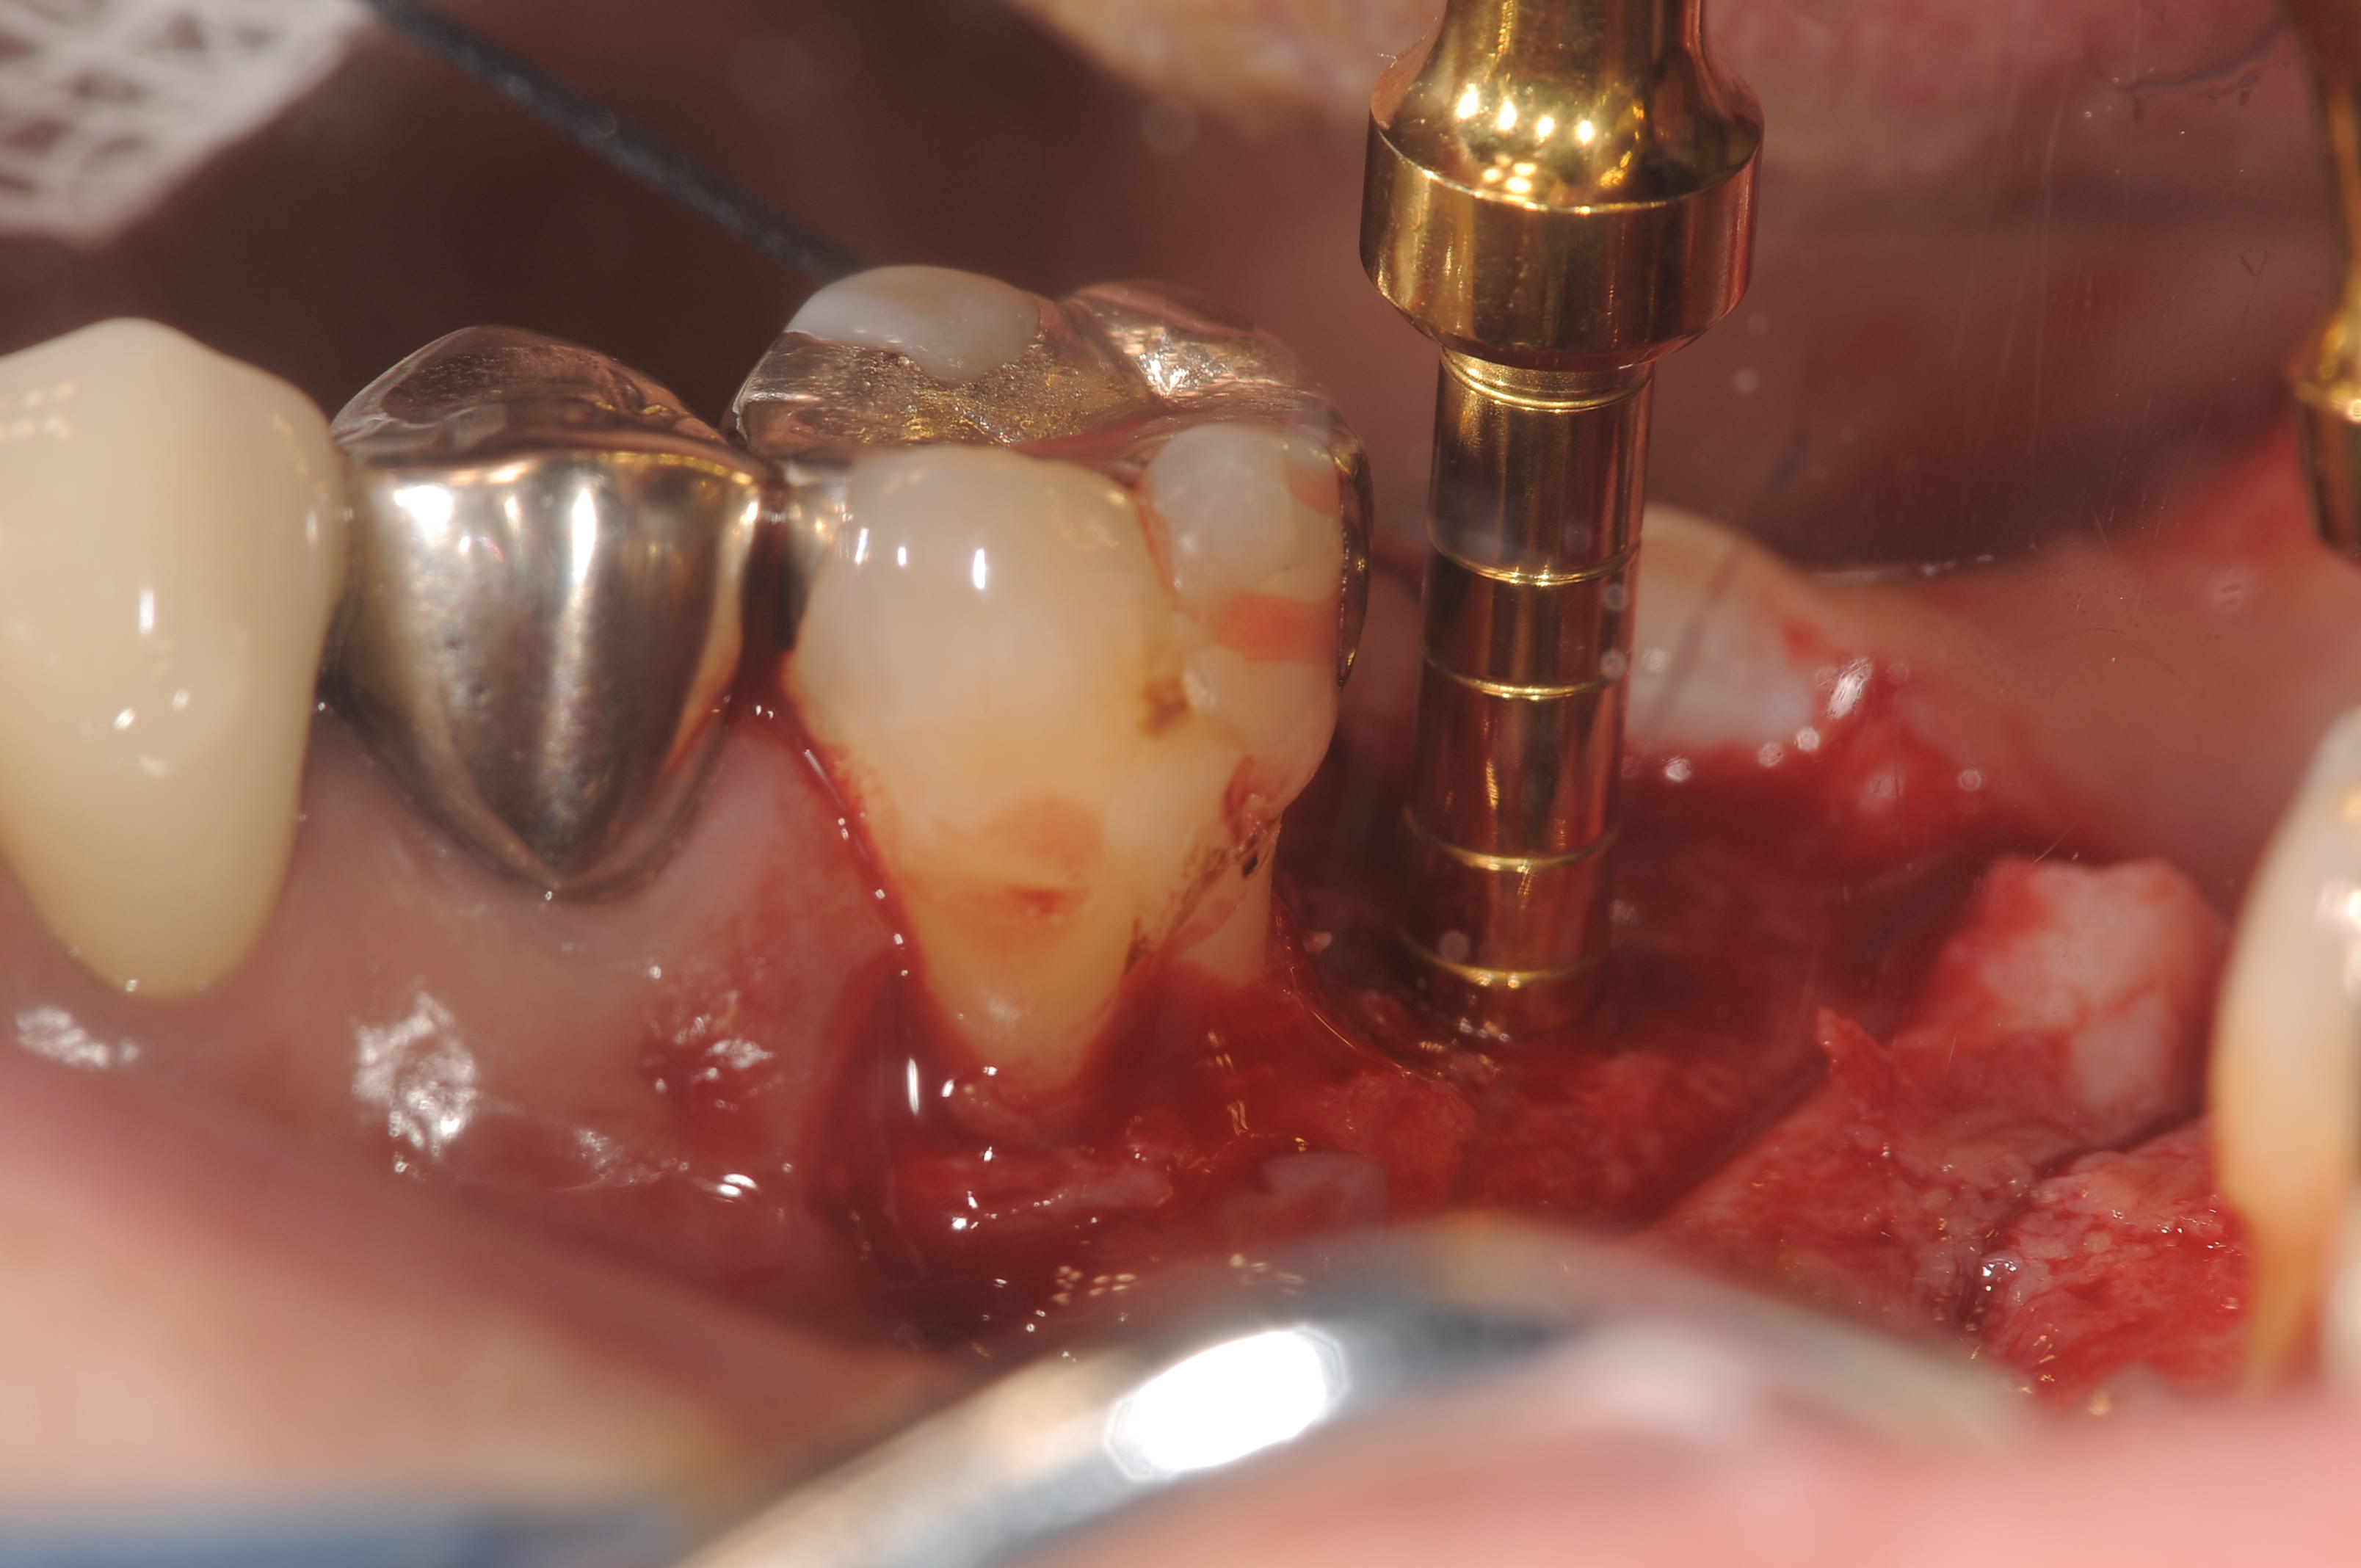

今日のオペは、上顎の第2大臼歯部の欠損に対して、ソケットリフトを行ってストローマン社のティッシュレベルのワイドネックインプラントを埋入しました。

サマーズテクニックで埋入窩を作っていきます。最終径は4.0mmΦです.

使用した補填材はβTCPです。

ストーローマン社製のインプラントでSLActiveです。